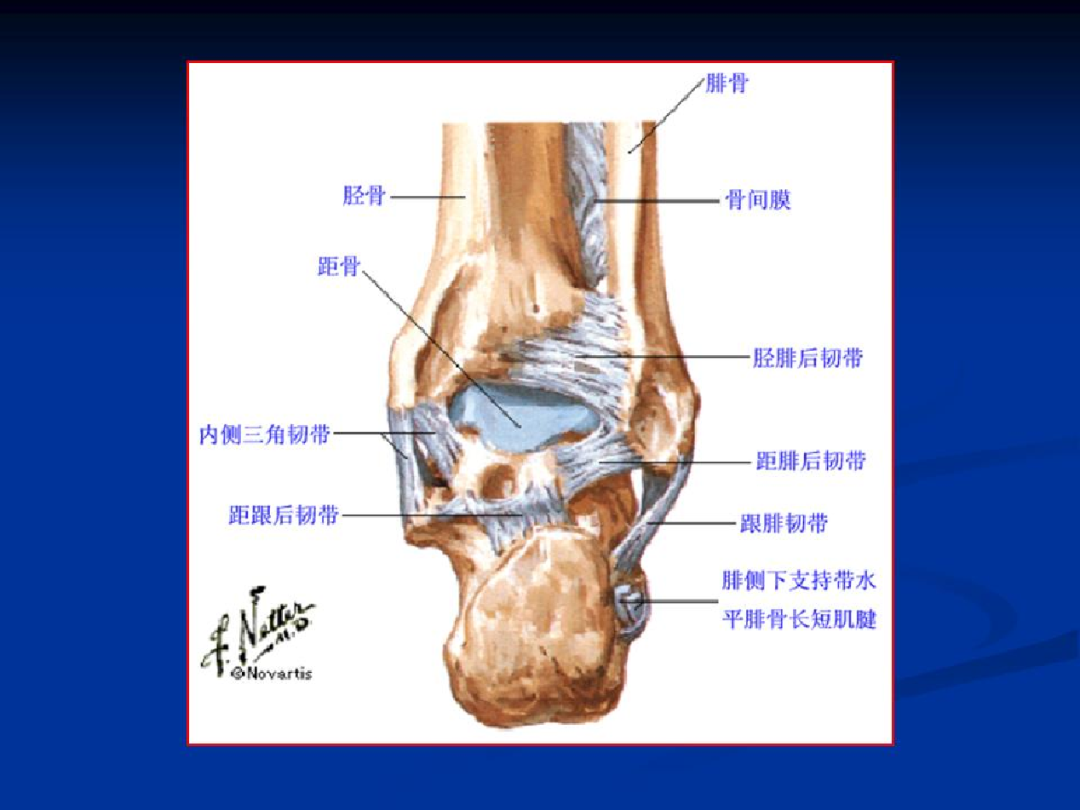

韧带

内侧三角韧带:胫距前、后韧带,胫跟韧带,胫舟韧带;

外侧韧带:距腓前韧带,距腓后韧带,跟腓韧带;

韧带复合体:胫骨前、后韧带,胫腓骨间韧带;

肌腱

外侧:腓骨长肌腱、腓骨短肌腱

内侧:胫骨后肌腱、趾长屈肌腱、踇长屈肌腱

前方:胫骨前肌腱、趾长伸肌腱、踇长伸肌腱

后方:跟腱